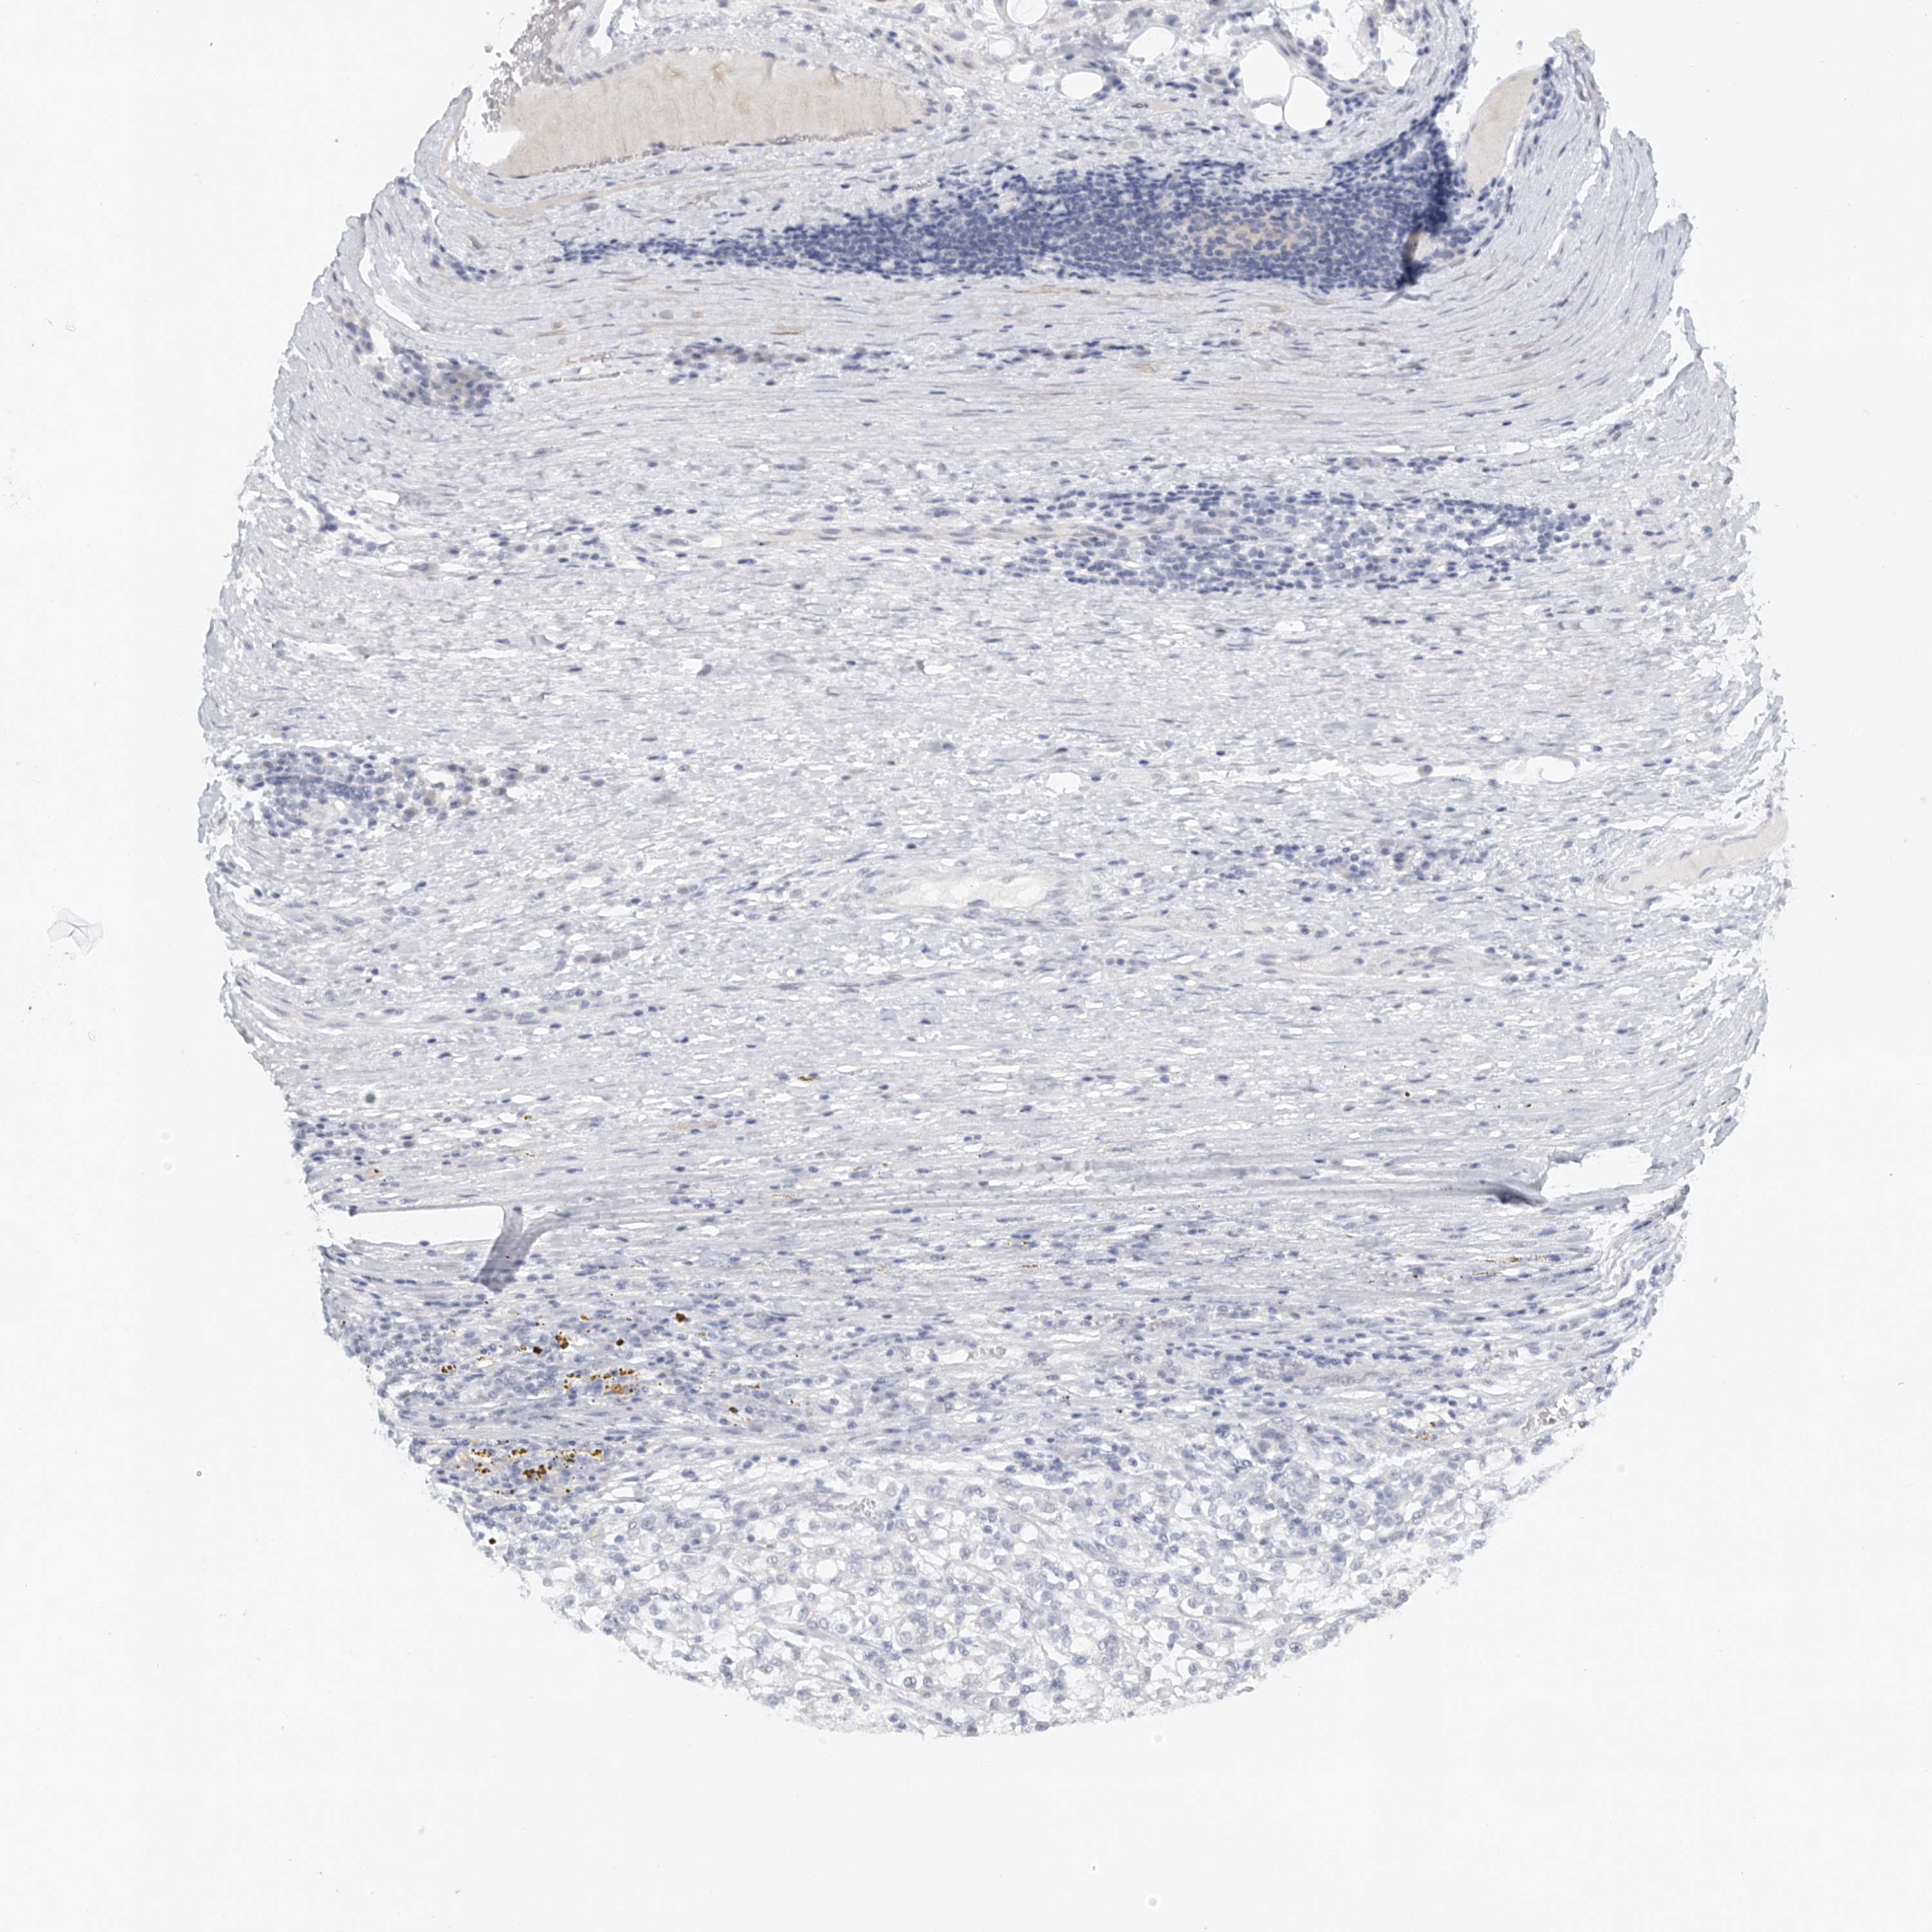

CANCER RENAL CANCER Show tissue menu

KICH TCGA KIRC TCGA KIRC VALIDATION KIRP TCGA PROTEIN RCC CPTAC PROTEIN EXPRESSION